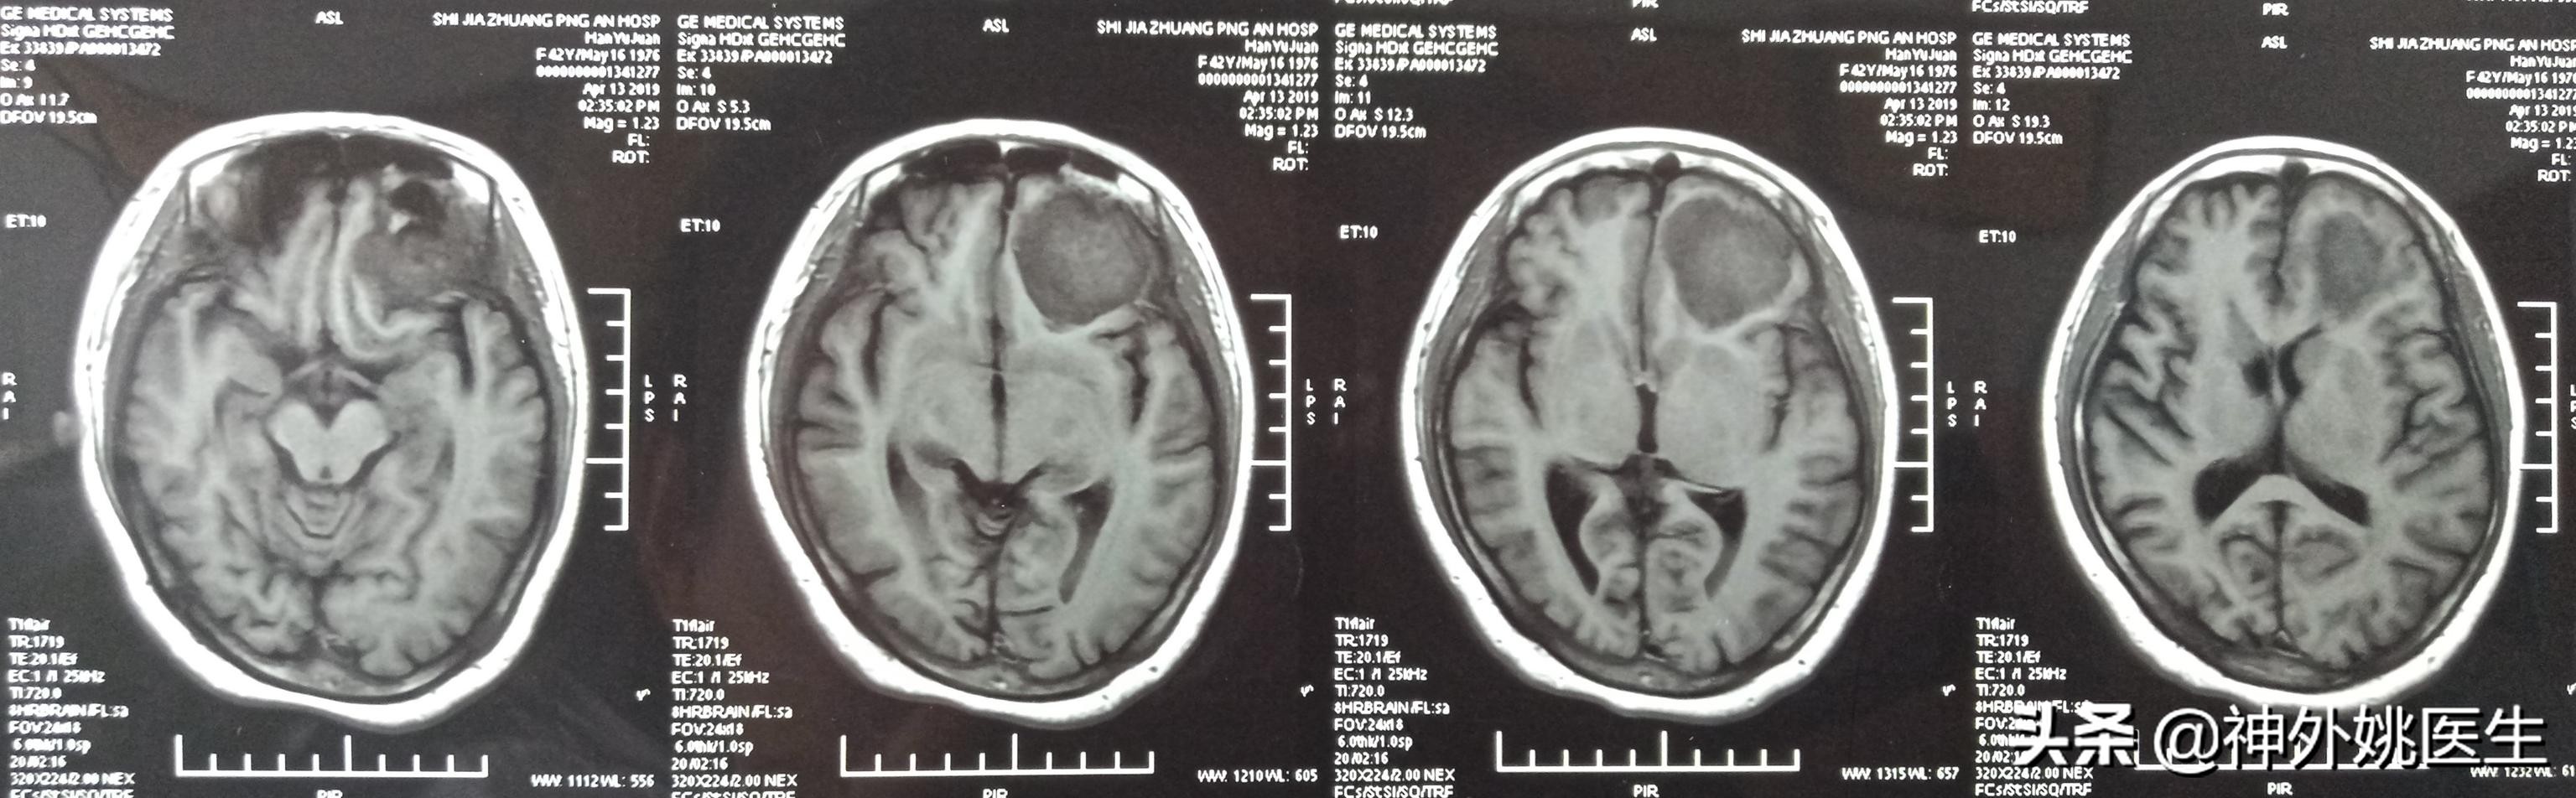

头MRI检查:1、左额部脑膜瘤。2、左侧放射冠区腔隙性脑梗死。(图3-7)

图3 T1像病变呈稍长T1信号。

图4 T1像病变呈稍长T2信号。